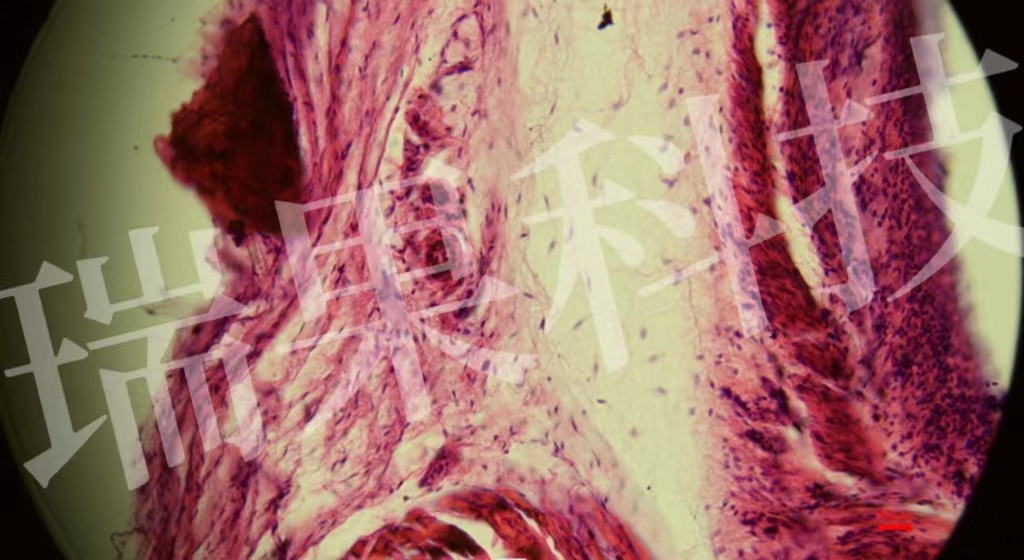

HE染色:苏木精 - 伊红染色法 ( hematoxylin-eosin staining ) ,简称HE染色法 ,石蜡切片技术里常用的染色法之一 。苏木精染液为碱性 ,主要使细胞核内的染色质与胞质内的核酸着紫蓝色 ;伊红为酸性染料 ,主要使细

HE染色:苏木精 - 伊红染色法 ( hematoxylin-eosin staining ) ,简称HE染色法 ,石蜡切片技术里常用的染色法之一 。苏木精染液为碱性 ,主要使细胞核内的染色质与胞质内的核酸着紫蓝色 ;伊红为酸性染料 ,主要使细胞质和细胞外基质中的成分着红色 。HE染色法是组织学、胚胎学、病理学教学与科研中最基本、使用最广泛的技术方法。

气管